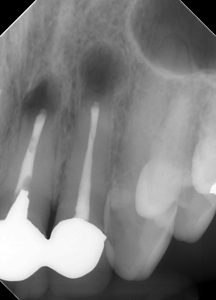

(治療直後のレントゲン、CT)

3本同時に手術を行った。

治療は1時間ちょっとで終了した。

逆根管充填をMTA→Lid Technique(BCシーラーとパテ)に変えてから、

治療時間が大幅に短くなった。

我々や患者さんにとっても、非常に大きな恩恵である。

レントゲン的に、仕上がりは問題ない。

ここから経過観察を行なっていった。